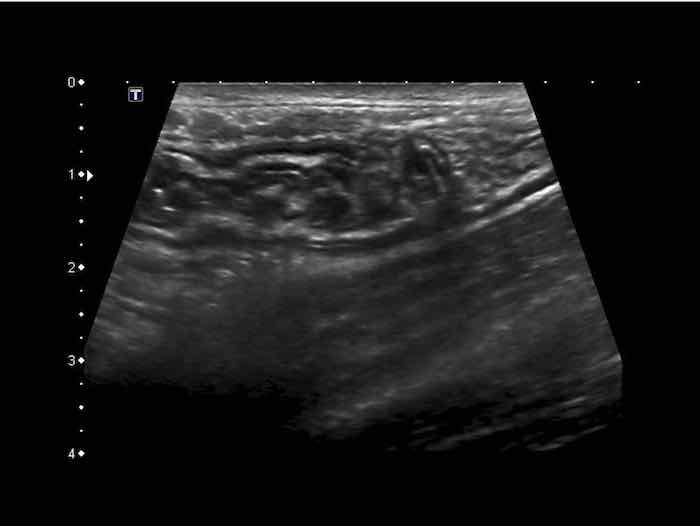

Đây là hình ảnh siêu âm của một trẻ 2 tuổi bị lồng ruột hồi manh tràng từng đợt, được khám trong khoảng thời gian giữa các cơn.

Hồi tràng với nhiều mảng Peyer sa vào manh tràng.

Hình ảnh siêu âm kinh điển của lồng ruột hồi-manh tràng ở hai trẻ khác nhau.

Trong cả hai trường hợp, đoạn hồi tràng bị lồng được định vị không đối xứng bên trong ống lồng ngoài, do mạc treo ruột tăng âm có chứa mỡ, bám vào hồi tràng và đi theo hồi tràng khi bị kéo vào trong.

Trong mạc treo, siêu âm cho thấy một hạch bạch huyết mạc treo (hbh) phóng đại ở cả hai.

Các hạch này phì đại như một phần của tình trạng tăng sản hạch bạch huyết toàn thân và khônghu trú trong lòng hồi tràng.

Do đó đây không phải là điểm dẫn đầu nguyên phát. Ở bệnh nhân bên phải, ruột thừa (mũi tên) cũng bị kéo vào trong.

Lưu ý cấu trúc đa lớp của thành bụng phía trước của phức hợp lồng ruột, đại diện cho ba lớp thành ruột bị gấp lại.